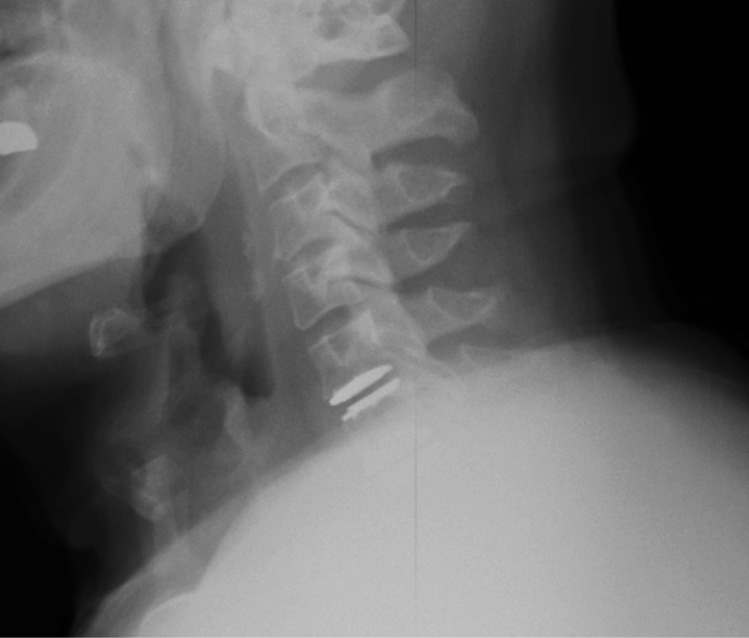

Pre-op MRI demonstrates partial disc height collapse and foraminal stenosis at C5-6 and C6-7.

Pre-op dynamic radiographs demonstrate partial loss of disc height at C5-6 and C6-7 without instability or scoliosis.

The patient’s symptoms have completely resolved. The x-rays in Figure 8 were taken at the first post-op visit at 2 weeks.